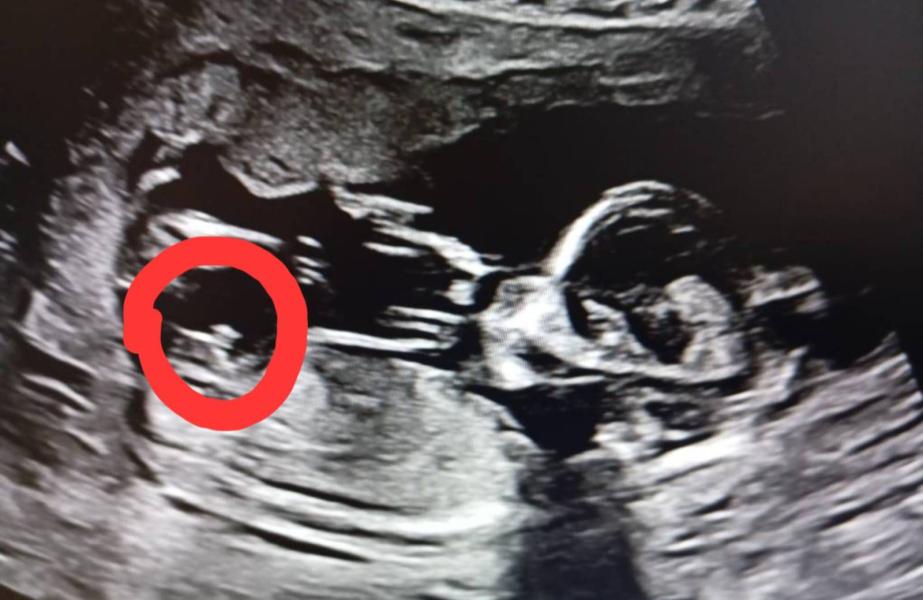

Определение пола ребенка с 13 недель: насколько достоверно?

Определить пол с большей достоверностью можно с 13 недель .

А как вам кажется кто здесь?

На фото девочка?